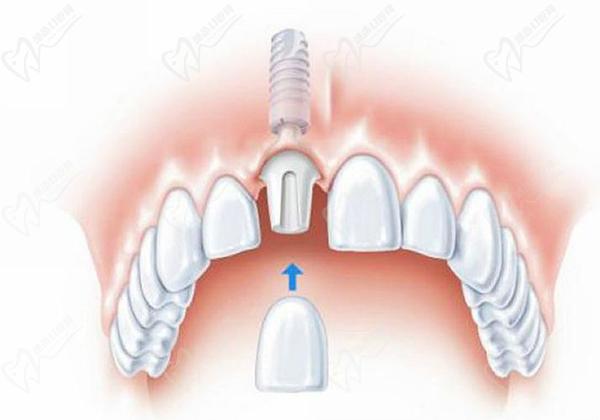

(5)即刻安裝愈合基臺:在種植體植入后,安裝愈合基臺以促進(jìn)軟組織愈合,并佩戴臨時牙冠。

(6)修復(fù)牙冠:在軟組織愈合后,進(jìn)行固定牙冠的更換,以恢復(fù)牙齒的外觀和功能。

是的,瑞士士卓曼種植牙可以直接帶牙冠。在種植體植入后可以做即刻修復(fù)佩戴牙冠,經(jīng)過一段時間的愈合,可以直接安裝永 久牙冠。所以,瑞士士卓曼種植體是非常適合用于即刻負(fù)重、即刻修復(fù)、半口全口疑難即刻負(fù)重種植中的,得益于其具備良好的初期穩(wěn)定性、親水性能好,骨結(jié)合速度快等特性。

(1)士卓曼即刻種植即刻修復(fù):瑞士士卓曼種植牙不需要通過傳統(tǒng)的橋式修復(fù)方式來恢復(fù)牙齒的外觀和功能,而是直接在種植體上安裝牙冠,更加舒適和美觀。大白話來說就是,拔牙的當(dāng)天就能種一顆或幾顆牙,完全不用戴可以摘的活動修復(fù)體,不管是佩戴臨時牙冠還是永 久牙冠,都媲美自然牙齒!